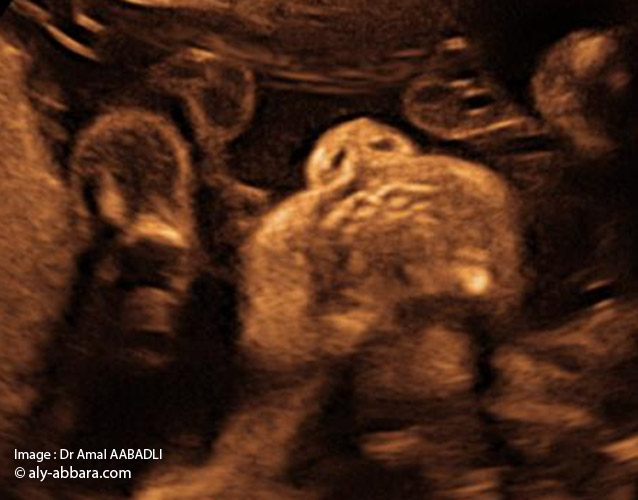

Coupe frontale de face : nez, bouche et menton_01

صورة الأنف الفم و الذقن

لا يكون إتمام فحص جنين ما دون فحص منطقة الأنف و الفم و الذقنً

يتم الحصول على هذه الصورة بقطعة تاجية للوجه و هذا يعني أن المسبار الصدوي يجب أن يوضع من الجبهة إلى الأسفل – نقول أيضاً قطعة جبهية و المعنى واحد- كأنه تاج. و يمكن أيضاً أن نوجهه من أسفل الذقن

هدف هذه الصورة هو التأكد من عدم وجود عَلَم شفهي

جهل وجود عَلَم شفاهي (شق الشفة أو فَلْح الشفة وكذلك، شفة الأرنب) يؤدي لجهل تشوهات كثيرة أخرى يمكن أن ترافق العلم ـ وهو سهل التشخيص -

و يمكن أيضاً أن يؤدي إلى صدمة الأم عند الوضع,لهذا فإن هذه الصورة أولية و ضرورية في الفحص

• La coupe échographique fœtale " nez, bouche et menton :

• L'étude morphologique du fœtus ne peut être complète sans l'examen de la région du "nez, bouche et menton".

• Pour obtenir cette image il faut effectuer une coupe coronale (frontale) sur la face, pour cela il faut diriger la sonde échographique posée sur le front du fœtus vers le bas du visage ; ou l'inverse, diriger la sonde posée sur le menton vers le haut du visage.

• Le but de cette image est de s'assurer de l'absence de fente labiale (bec de lièvre).

• Passer à côté du diagnostic de la fente labiale aboutit à l'ignorance d'autres malformations pouvant être associées à cette anomalie de la face, et pourtant c'est un diagnostic facile et nécessaire d'être fait afin d'éviter le choc qui peut être ressenti par la mère à l'accouchement en voyant son nouveau-né atteint par cette malformation, d'où l'intérêt capital de réaliser cette iconographie échographique lors de l'examen échographique du fœtus.